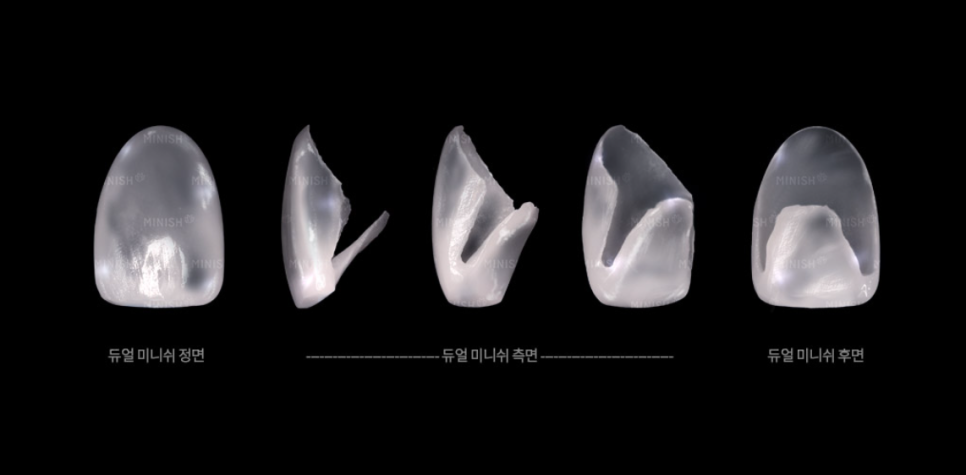

Because the patient had widespread cavities along with wear, erosion, cracks, and staining, treatment was performed using the Dual MINISH method, which covers both the front and back surfaces of the teeth. This can be considered in cases where broad damage exists and the patient wishes to restore function and aesthetics while aiming to minimize additional tooth reduction.